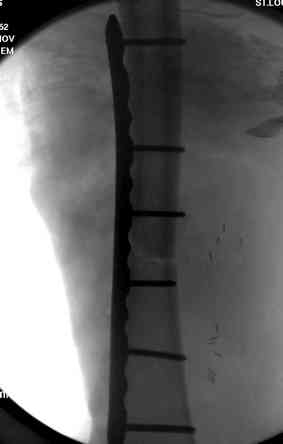

Я бы выполнил более стабильную фиксацию (а у меня есть подозрения в нестабильности отломков - компоновка минимальная, стержни проведены близко друг от друга, имеется выраженное воспаление тканей вокруг раны). Добавил бы стержни в данном аппарате или бы наложил спицестержневой аппарат.

Может, данное наблюдение поможет в принятии решений в подобных ситуациях.

Огнестрельный дефект костей и передней группы мышц, поступил с юнилатеральным аппаратом, стабильность плохая, из раны обильное гнойное

отделяемое. #1;#2. Стержневой апп. снят, наложен апп. Илизарова, дренажно-ирригационная система промывки раны. #3; #4. После стихания инфекции,

аппаратом постепенно создана рекурвация для сближения контактов мышц (сухожилий) передней группы голени. #5;#6. Наложен шов на сухожлилия М.

Tibialis anterior и M extensor digitorum L. Одновременно компактотомия костей голени в В/3 для замешение дефекта костей. #7;#8. Постепенно

исправлена ось и возмещен дефект. В результате восстановление тыльной флекcии стопы и функции конечности. #9;#10;#11